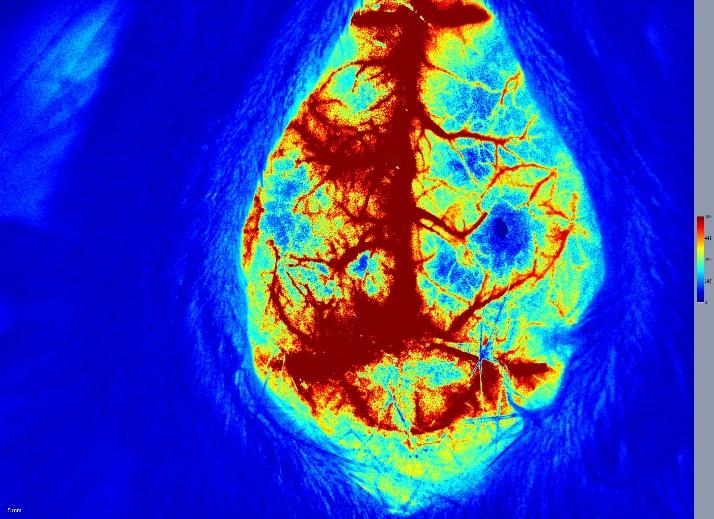

脑卒中

缺血再灌注性脑卒中模型MC…

光化学诱导的缺血性脑卒中…

胶原酶诱导的出血性脑卒中…

永久缺血性脑卒中模型